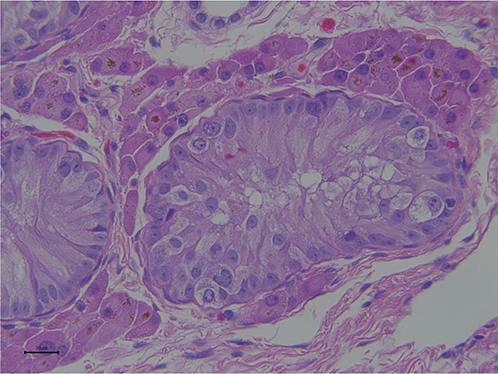

Histopathology of retained testis

Because of the lack of appropriate testicular thermoregulation, the undescended testis undergoes several histological and endocrine disturbances.54,55 A 45% and 31% reduction in seminiferous tubules density was observed in abdominal and inguinal testes respectively, compared to a normal descended testicle.56 On histopathology seminiferous tubules have a wider lumen with vacuolation of the cells within the seminiferous epithelium (Figure 7). Seminiferous tubules may be poorly differentiated and appear as solid cords with Sertoli cell cytoplasm filling the tubules (Figure 8). Some tubules are lined by only 1 or 2 layers of spermatogonia. In inguinal retained testes, germ cells can be found at different stages of maturation but not beyond the stage of secondary spermatocytes, whereas in abdominal testes spermatogenesis is arrested at type A or B spermatogonia.55,57,58 A few spermatogonia and occasional degenerating primary spermatocytes may be present in some cases.40 Atypical germ cells may be seen in the basal area of the seminiferous tubules.53 The population of Leydig cells observed in cryptorchid testes is similar to that of the scrotal testes.56

Fig. 7.

Figure 7. Photomicrograph of a section of an abdominal testis: ST = seminiferous tubules showing vacuolization, arrow indicates Leydig cells (H& E stain; Bar = 100µm).

Fig. 8.

Figure 8. Photomicrograph of a section of an abdominal testis. The seminiferous tubule is filled with the cytoplasm of Sertoli cells (H& E stain; Bar = 20µm).

With advancing age, the testicular parenchyma of the retained gonad undergoes further degenerative changes and fibrosis with increase thickening of the albuginea. These changes are more pronounced in abdominal than in inguinal testes.56,59,60 Severe testicular compromise following torsion of the spermatic cord may lead ischemia,59,61,62 tissue necrosis and atrophy, which may sometimes be confused with true monorchidism, a much less common condition.6367

Histochemical studies of cryptorchid testes revealed a disruption of the morphology and histochemistry of both Leydig and Sertoli cells. Leydig cells are poorly differentiated and have a deviation in α-actin expression.59 Sertoli cells of cryptorchid testes show degenerative changes and alteration of the distribution of vimentin, a component of the intermediate filaments postulated to play an important role in regulation of spermatogenesis.59,68,69